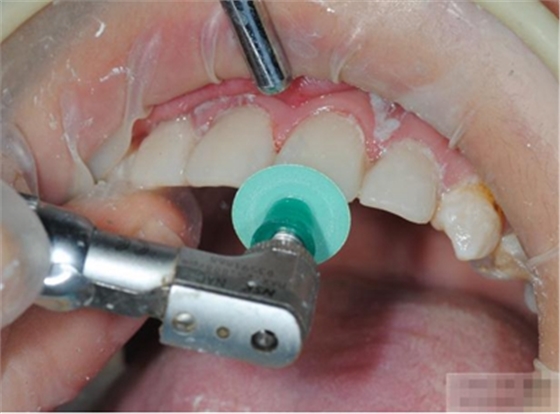

釉質(zhì)邊緣要用橡皮輪拋光

拋光可以去除懸釉。這樣經(jīng)過車針打磨過的釉質(zhì)表面會(huì)更加均一,形成良好的邊緣封閉。